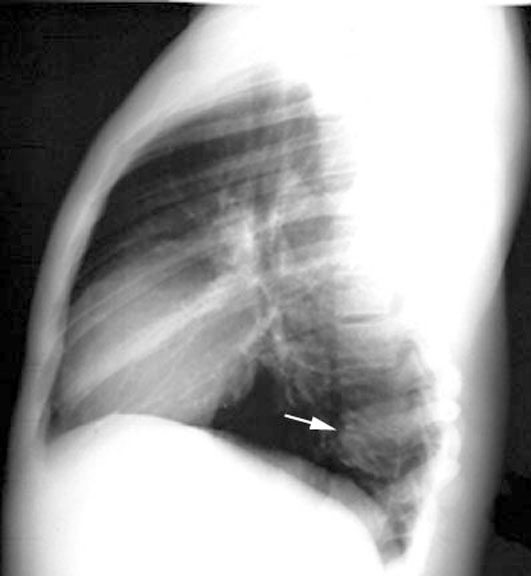

| CXR | Are both diaphragms visible in lateral view? | What is the significance if one diaphragm is not visible? | Answer |

| CXR | Identification of side of abnormality | If one diaphragm is not seen how do you determine which side is abnormal? | Answer |